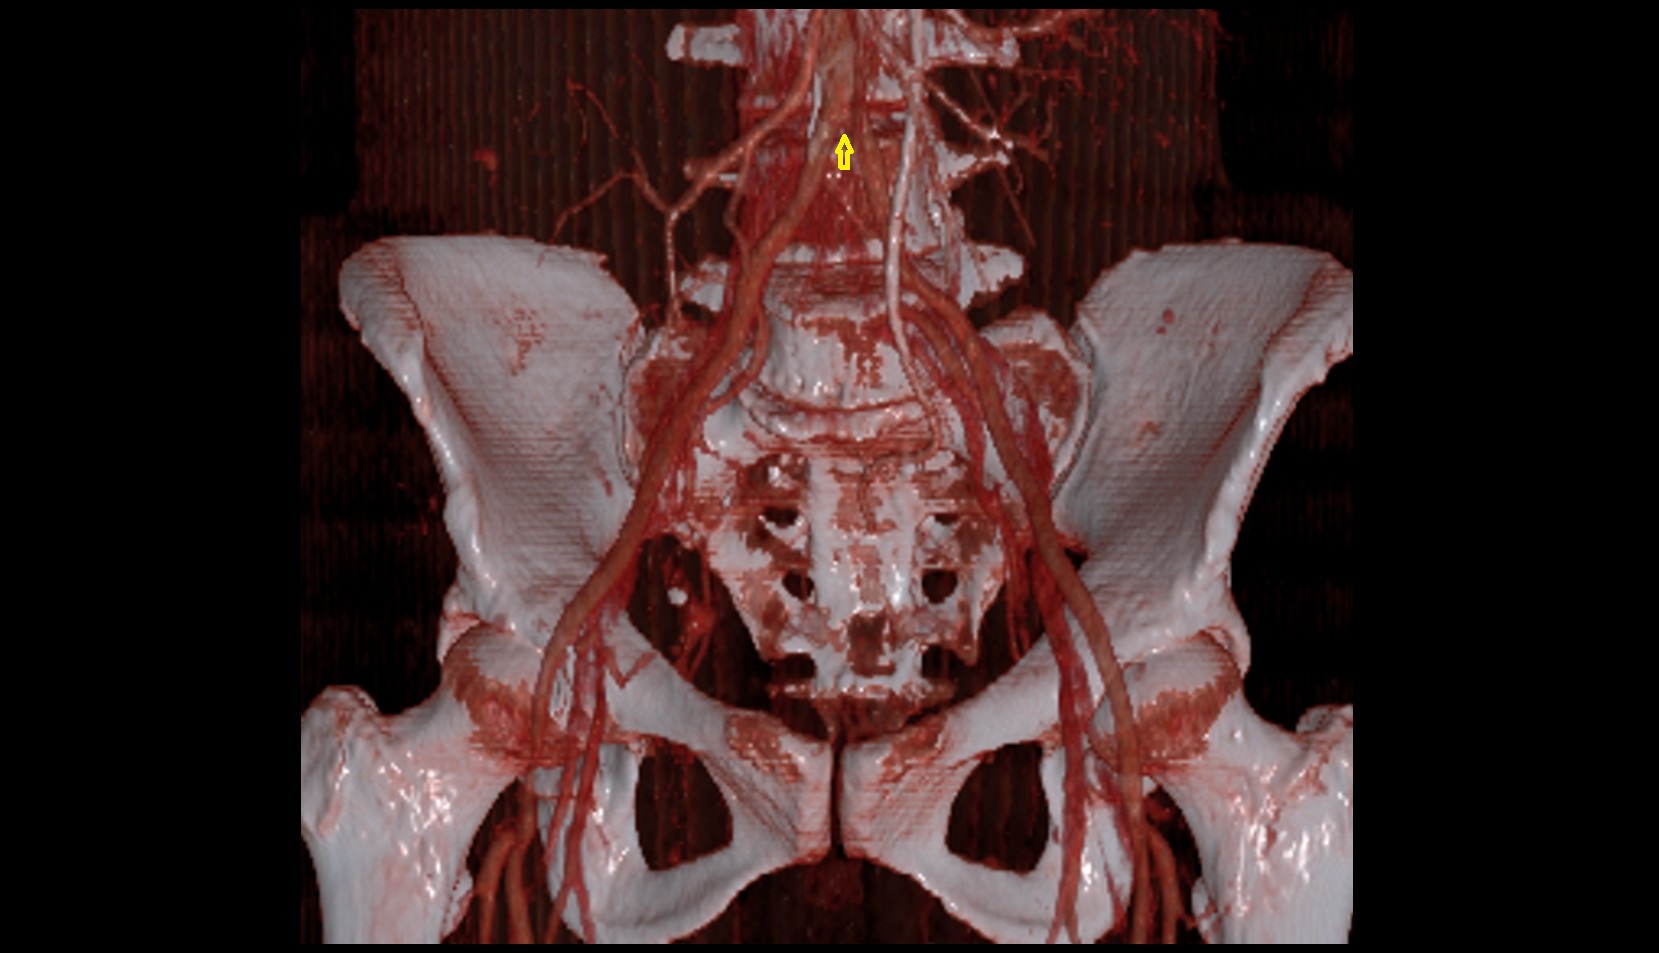

- Aortic bifurcation

- External iliac artery

- Internal iliac artery

- common iliac artery

- Femoral artery

- Medial circumflex femoral artery

- Obturator artery

- Superior gluteal artery

- Deep circumflex iliac artery

- Inferior gluteal artery

- Lateral circumflex femoral artery

- Deep femoral artery (profunda femoris)

- External iliac vein

- Femoral vein

- Common iliac vein

- Union of common iliac veins